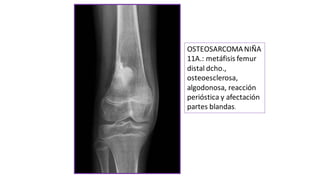

OSTEOSARCOMANIÑA

11A.: metáfisis femur

distal dcho.,

osteoesclerosa,

algodonosa, reacción

perióstica y afectación

partes blandas.